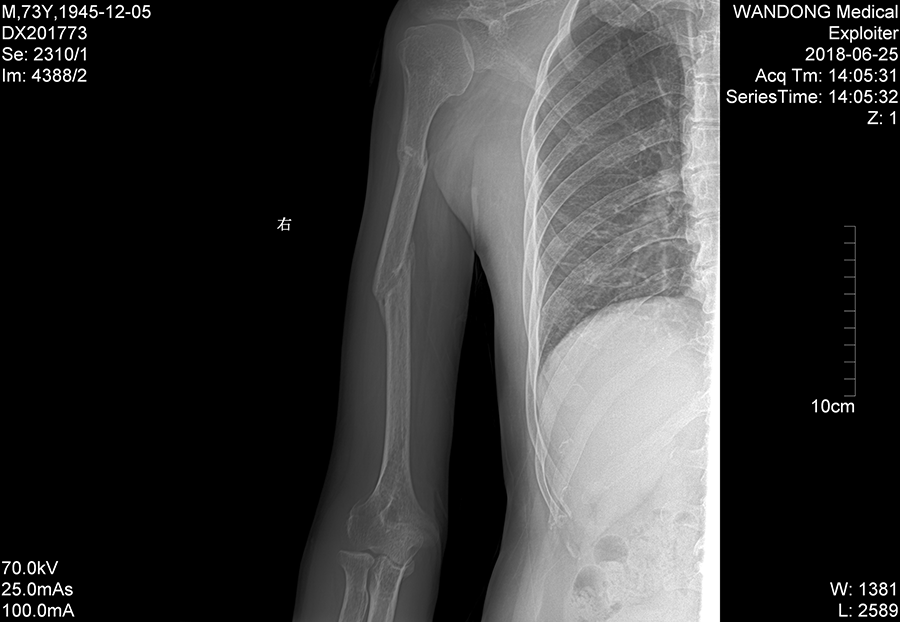

经过半个月小心治疗后,李大伯的手臂肿胀消退,伤情稳定下来,而后继续绑固治疗并辅助相关药物。8周后再次拍片,伤肢已经没有疼痛感,经拍片显示有较多骨痂形成,可以拆除夹板了。又再次小心嘱咐李大伯,要逐渐加强伤肢的功能训练,避免过早用力,估计半年左右就能痊愈了。

“最适合的治疗才是最好的治疗,要根据患者的具体情况,精准施治。”这是陈主任一直遵循的理念。陈主任常说:我们当医生,要多站在病人的角度考虑,尽量采用微创保守的治疗办法,严格掌握手术适应症,要为真正需要手术的病人手术。